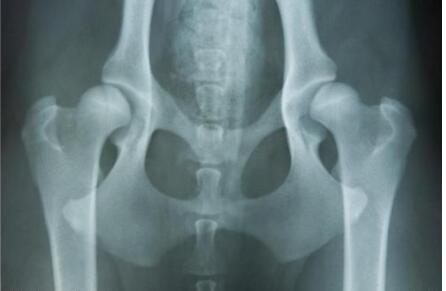

7. 遗传性关节炎。纯种狗近亲交配繁殖比较多,狗狗的髋关节炎大多与遗传有关,父母任何一方出现过髋关节发育异常,那么近亲繁殖的纯种狗得遗传性髋关节炎的机率就非常高。